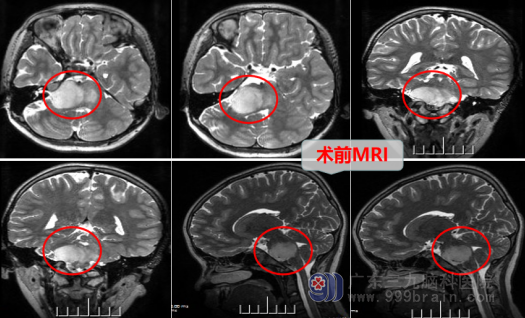

10岁的小锐(化名)性格活泼开朗,每天都会和小伙伴们玩耍打闹,家里人都说他精神好,有使不完的劲。但大概半个月前,小锐从外面玩耍回来以后,说自己头很晕。爸妈没有在意,以为小孩子调皮捣蛋,玩的太久,就让他尽快洗澡,早点睡觉。小锐刚准备忍着难受去洗澡时,一转身就呕吐了,爸妈立马警惕起来,赶快将他放到床上平躺。过了一会儿,孩子说还是头很晕,爸妈也觉得小孩子可能是感冒头晕呕吐,不会生什么大病,便抱去就近医院。医生问诊、查体后,建议其做头部MR检查,这时家属也担心怕小孩有什么大病,同意行MR检查,检查结果让大家大吃一惊,磁共振提示:脑干桥脑占位病变。

来到广东三九脑科医院,找到欧阳辉教授后,教授热情地接待了他们,门诊拟“脑干占位”收治,顺利办好了入院。住院后同时完善了一系列相关脑干肿瘤的检查,在制定完备手术方案并征得家属的同意后,小锐接受了脑干胶质瘤手术,手术在智能高清晰显微镜下进行,全程行神经电生理监测,术呈顺利,神经功能保护完好。小锐术后当天转入重症监护病房监护治疗,第2天由于病情平稳,即由ICU转回外十科普通病房,现小锐日渐好转,病房里又恢复了欢声笑语。